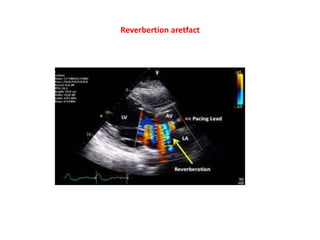

Reverbertion aretfact pelvic scan

Reverbertion aretfact